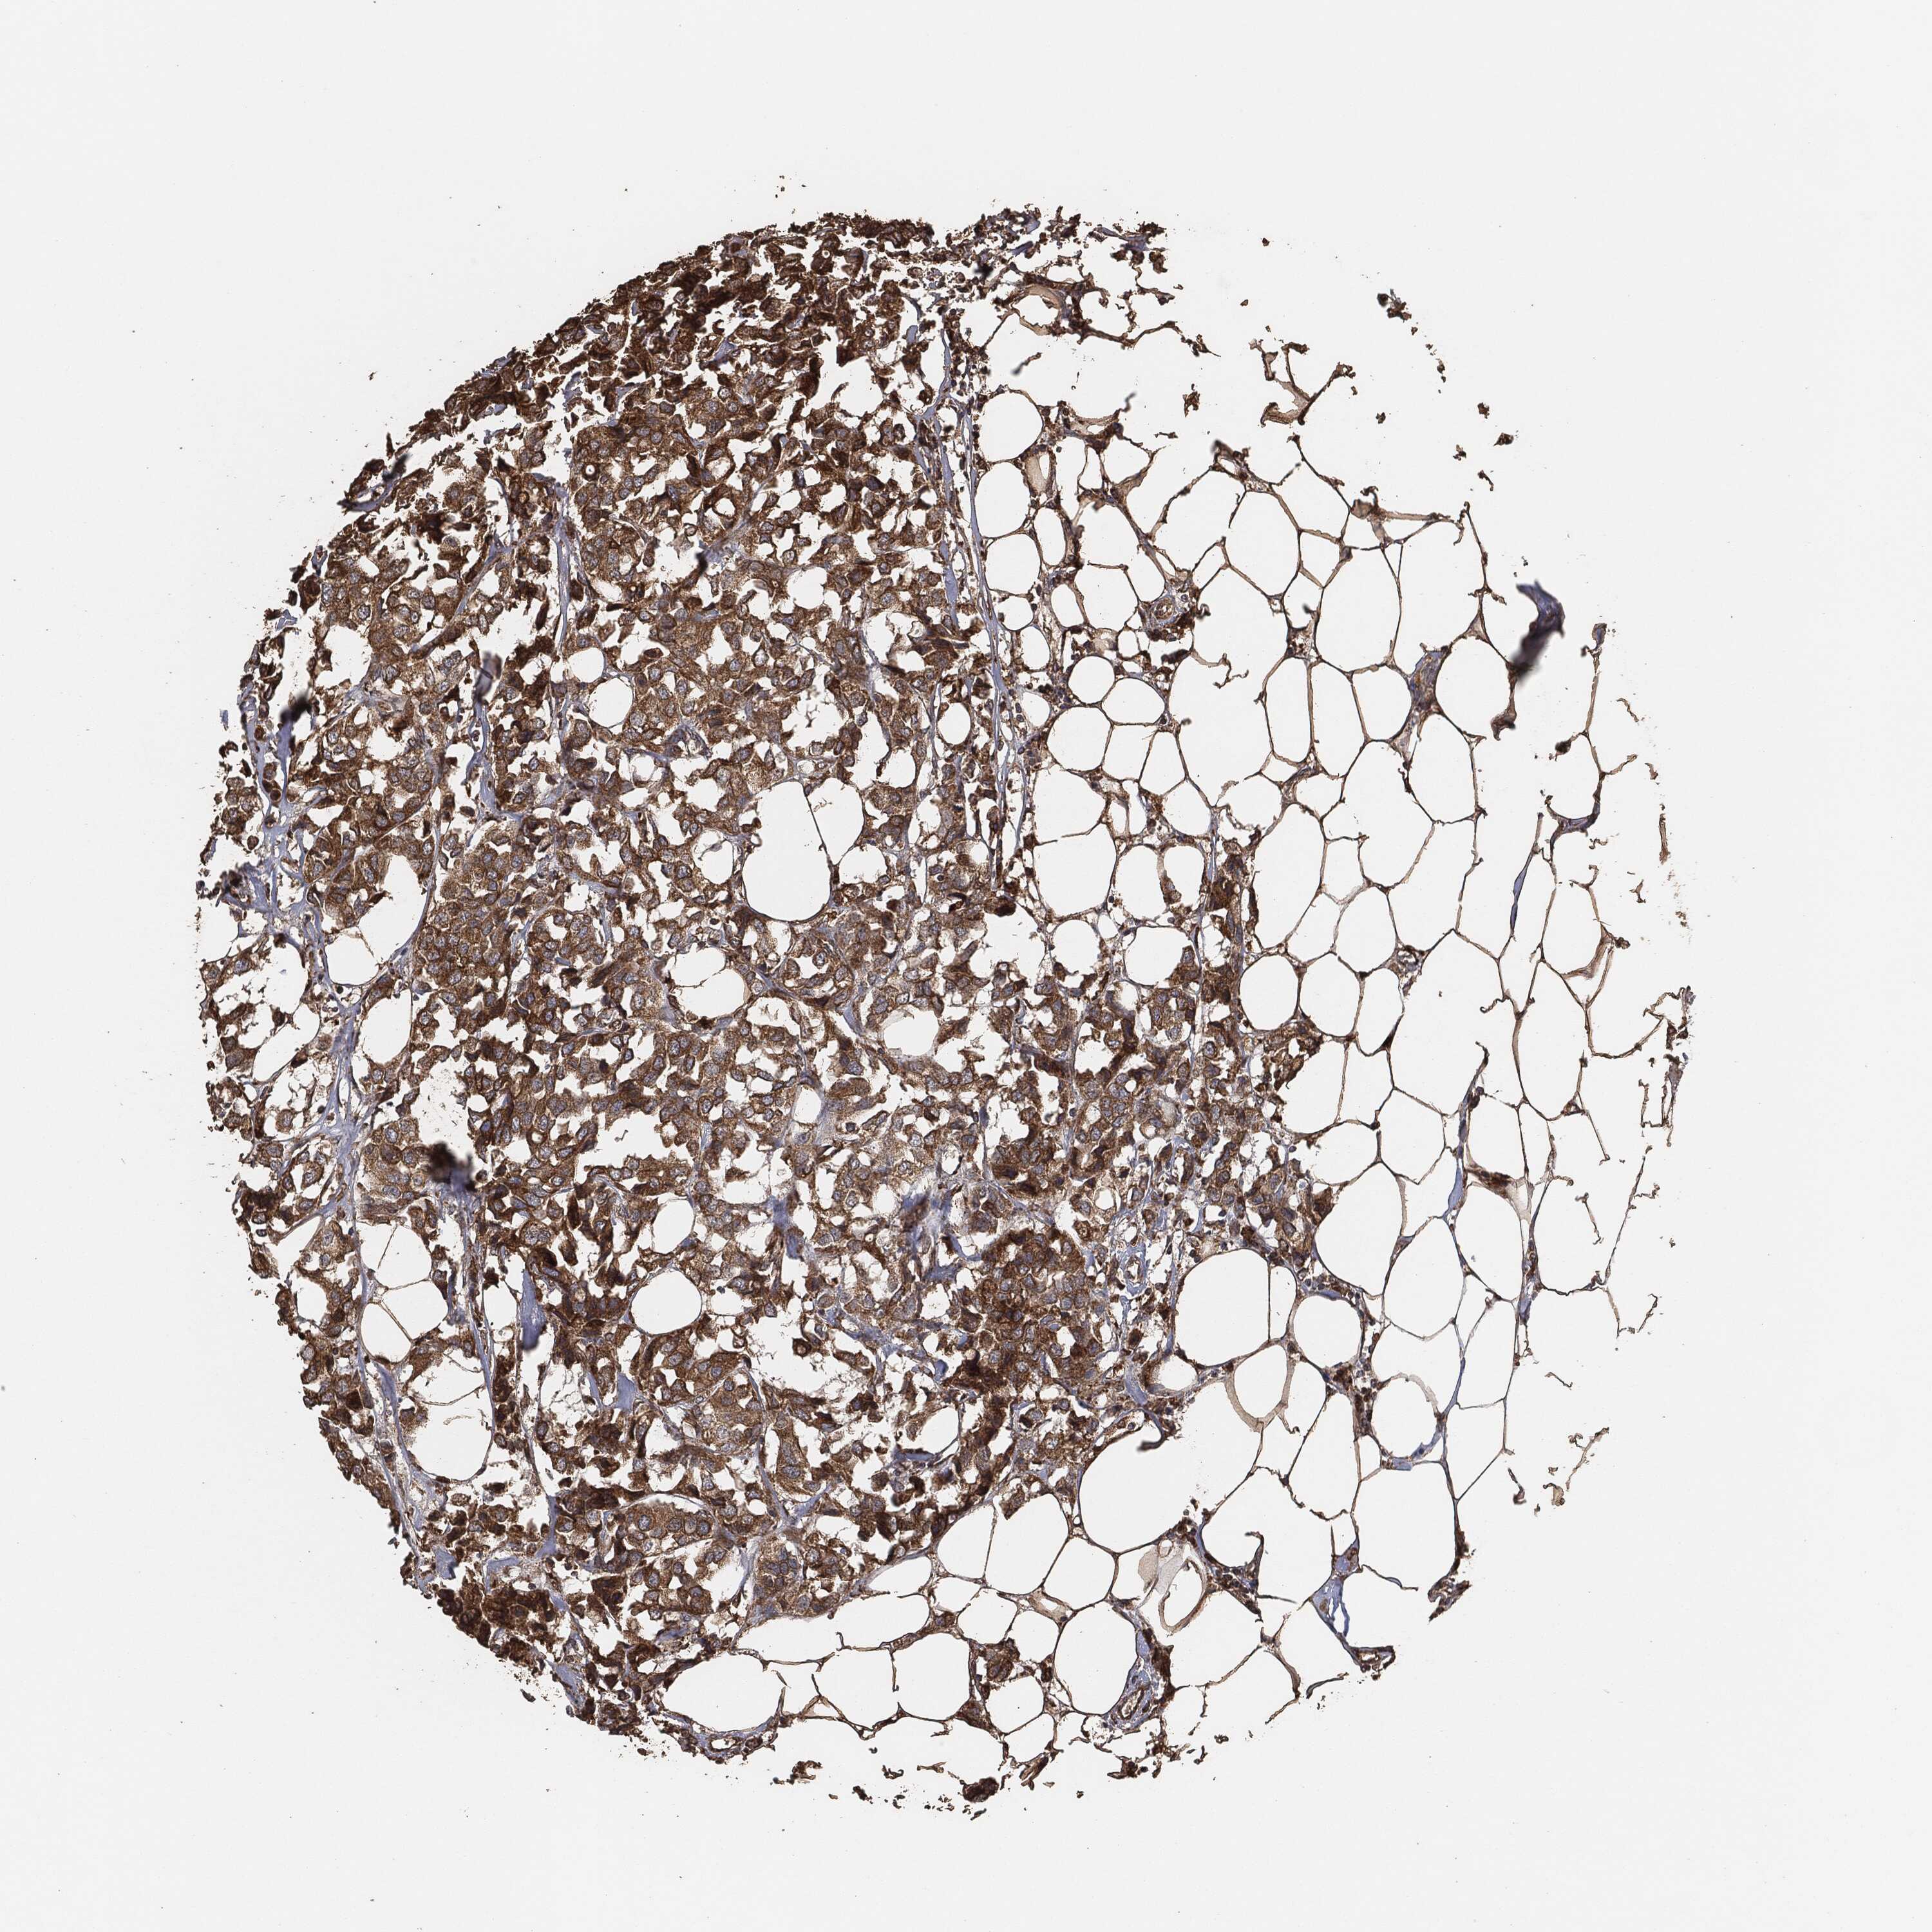

BRCA TCGA BRCA VALIDATION PROTEIN EXPRESSION